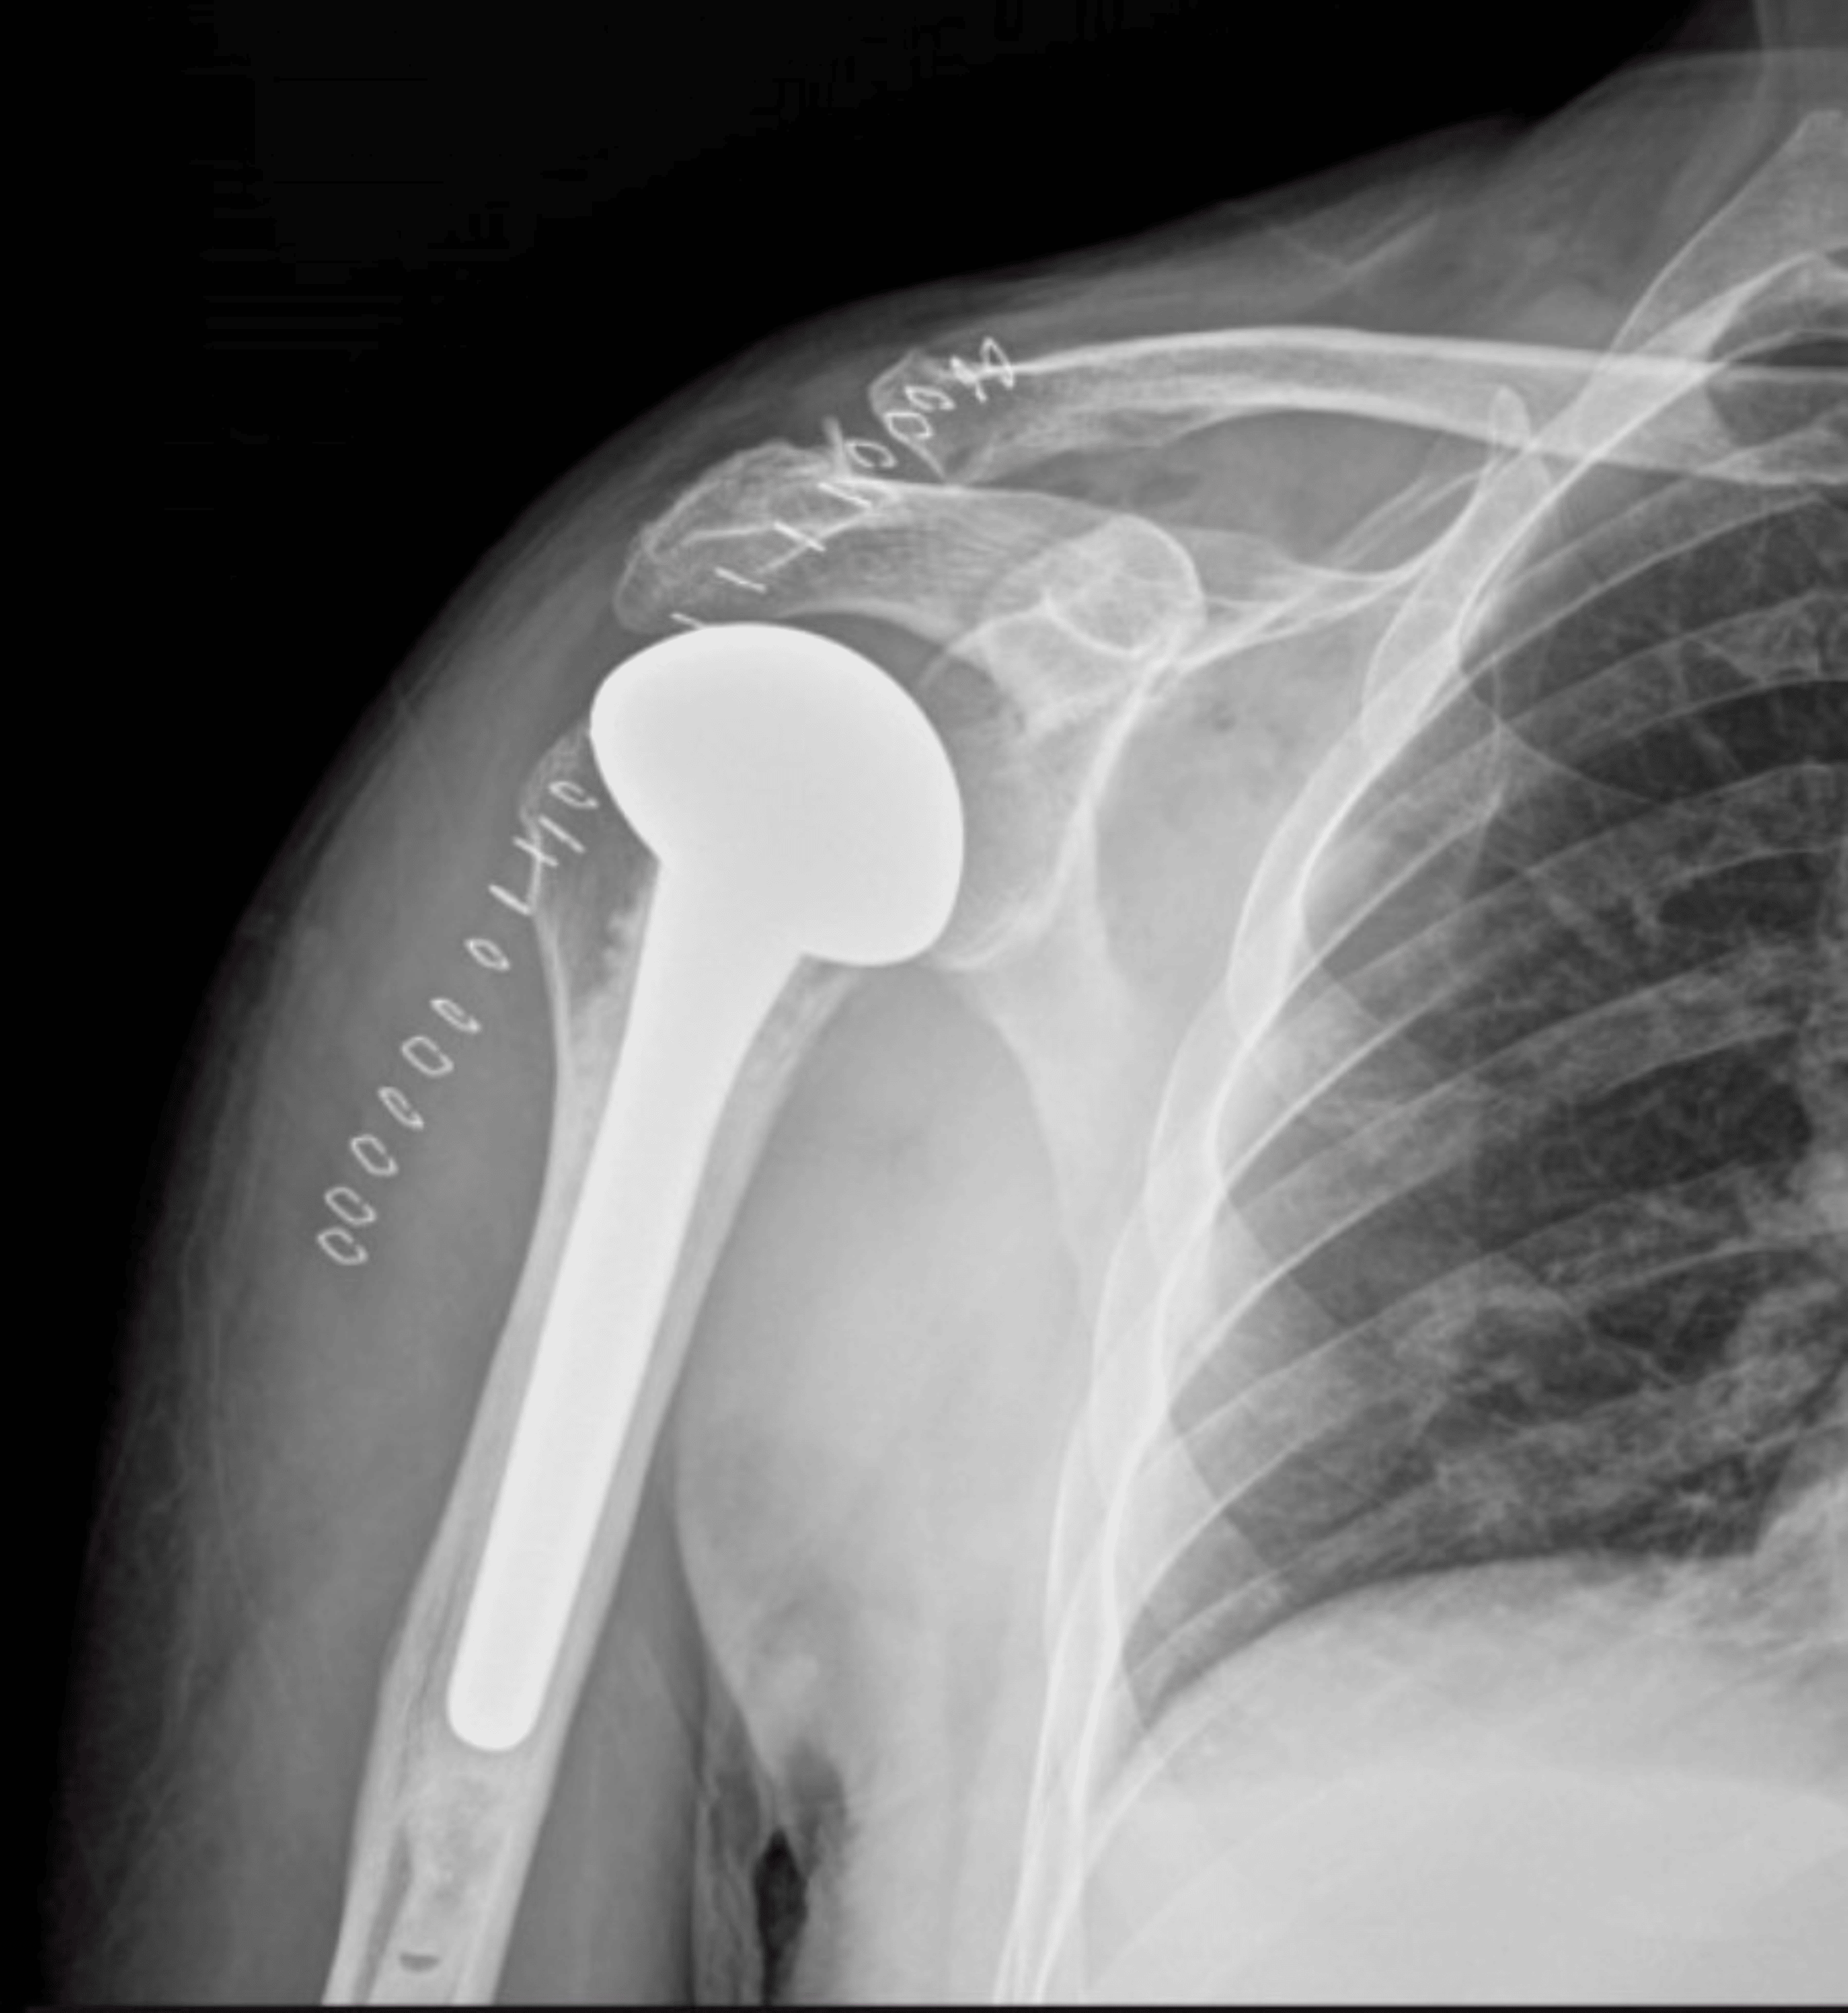

Light Bulb Sign Posterior Dislocation . Posterior shoulder instability and dislocations are less common than anterior shoulder instability and dislocations, but are much more commonly missed. Traditionally clinicians are taught to look for the ‘light bulb’ sign on anteroposterior (ap) radiograph as pathognomonic of a posterior. The light bulb sign refers to the abnormal appearance of the humeral head in posterior shoulder dislocation. The ‘light bulb sign’ suggests a posterior shoulder dislocation (figure 3). The smooth appearance of the internally rotated humeral head has been likened to a light bulb, so a posteriorly dislocated humeral head locked in internal rotation has been called the light bulb sign.

Posterior shoulder instability and dislocations are less common than anterior shoulder instability and dislocations, but are much more commonly missed. The light bulb sign refers to the abnormal appearance of the humeral head in posterior shoulder dislocation. The ‘light bulb sign’ suggests a posterior shoulder dislocation (figure 3). Traditionally clinicians are taught to look for the ‘light bulb’ sign on anteroposterior (ap) radiograph as pathognomonic of a posterior. The smooth appearance of the internally rotated humeral head has been likened to a light bulb, so a posteriorly dislocated humeral head locked in internal rotation has been called the light bulb sign.